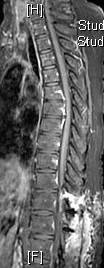

CLIPPERS综合征全称“类固醇激素反应性慢性淋巴细胞性炎症伴脑桥血管周围强化症”,是指在脑桥、中脑及小脑血管周围以淋巴细胞浸润为主、对类固醇激素治疗有效的慢性炎性疾病。该综合征由Pittock等于2010年首次报道,目前世界各地共报道100多例,国内报道不超过20例。其典型的头颅MRI增强检查示脑桥血管周围呈“胡椒粉”样斑点状强化病灶。本例患者MRI图像,与经典的CLIPPERS综合征影像不符合,强化灶并非以脑桥最密集,而是脊髓更显著,并且累及脊髓全长达腰膨大,双侧基底节脑室旁多发病灶,而且患者颅内受损的症状并不明显,这与文献报道的典型的CLIPPERS综合征并不符合。

治疗前                         治疗后

本例患者颅内病灶散发,脑活检的成功率可能不高,神经中心武剑主任和王贵怀主任对患者进行了详细的评估,经与患者家属充分沟通后,成功对该例患者进行了脊髓活检,手术顺利完成,术后患者无不适反应,病理结果回报符合典型的CLIPPERS综合征的表现,可除外脊髓结核、肿瘤等。至此该患者诊断CLIPPERS综合征明确,给与足量的激素冲击治疗后患者的临床症状明显缓解,复查MRI提示颅脑和全脊髓异常强化病变明显减少,并且强化程度减低,患者可独自站立,脊髓活检处手术切口愈合好。目前患者仍在密切门诊随访中。